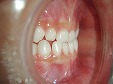

~修復後拡大~

オールセラミック修復

~術前~